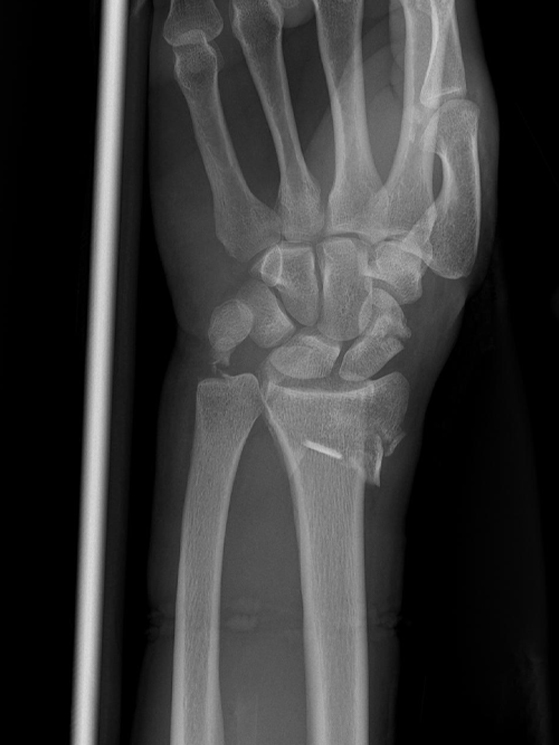

La sera stessa della caduta ho scritto al chirurgo che mi ha operato lo scorso anno (il dottor Pegoli, ndr). Appena ha visto la lastra ha capito che non si trattava solamente di una frattura del radio, ma l’osso era rotto in tre punti diversi. Inoltre, come se non bastasse, si è notata anche una frattura dell’ulna e dello scafoide. Praticamente cinque fratture al posto di una.

La frattura dell’ulna non permetteva di inserire una placca. Quindi i legamenti dovevano rinforzarsi in autonomia e per farlo ci vogliono, in media, sei settimane. Sono tornato in gara al Gran Premio Hindurain e poi al Giro dei Paesi Baschi. Il mio allenatore (Luca Quinti, ndr) è stato bravo a capire come resettare tutto in vista del Giro d’Italia. Dopo le corse in Spagna sono stato due settimane in altura a Sierra Nevada.